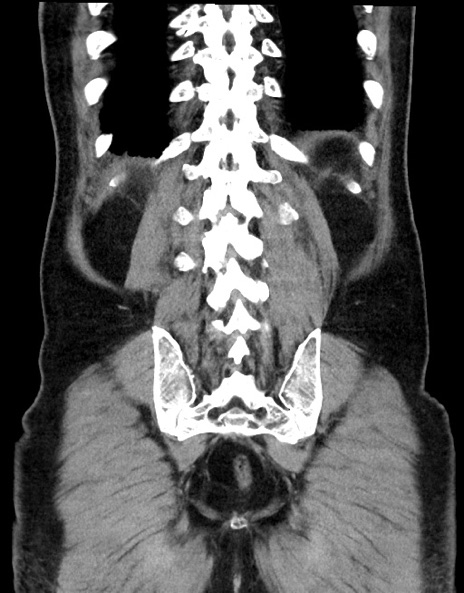

症例15(冠状断像)

【症例】70歳代男性

【主訴】腹痛

【現病歴】今朝から腹痛あり。全体的に痛い。特に左上の方。排ガスが今日はない。冷や汗が出る。

【既往歴】直腸癌術後

【身体所見】左側腹部〜上腹部に圧痛あり。腹膜刺激症状明らかなではない。軽度反跳痛。左下腹部に術後瘢痕あり。

【データ】WBC 7700、CRP 0.02